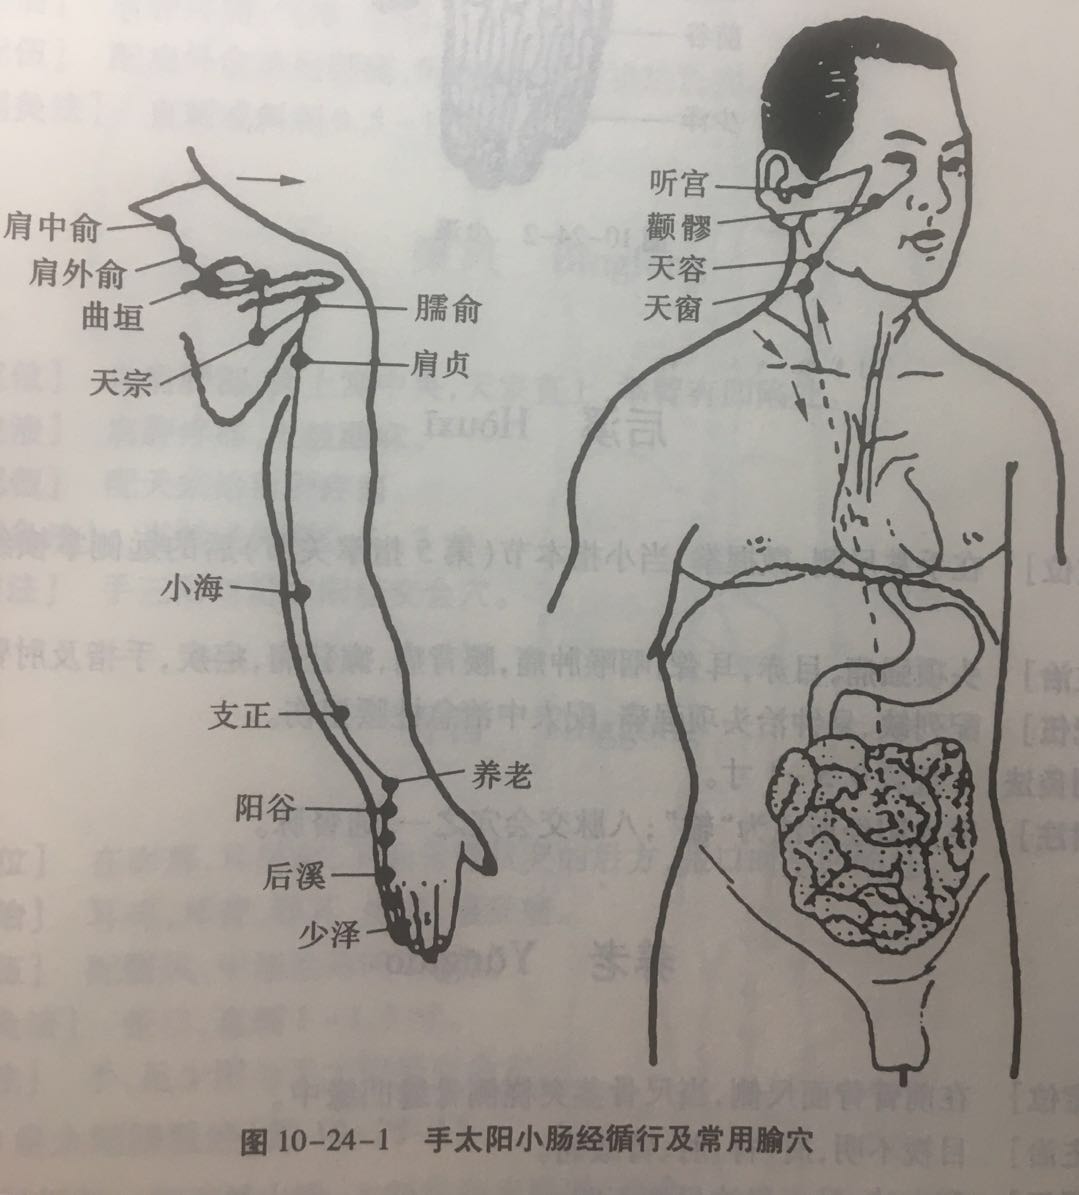

【(六)手太阳小肠经(图10-24-1)】

1、时辰 未时 13 ~ 15

2、歌诀 手太阳经小肠穴,少则先行小指末,前谷后溪腕骨间,阳谷须同养老列,支正小海上肩贞,臑(nào)俞天宗秉风合,曲垣肩外复肩中,天窗循次上天容,此经穴数一十九,还有颧髎(liáo)入听宫。

3、经脉循行 起于手小指外侧端(少泽),沿手背外侧至腕部直上沿前臂外侧后缘,经尺骨鹰嘴与肱骨内上髁之间,出于肩关节,绕行肩胛部,交于大椎(督脉)向下入缺盆部联络心脏,沿食管过膈达胃,属于小肠。

缺盆部支脉:沿颈部上达面颊,至目外眦(zì),转入耳中(听宫)。

颊部支脉:上行目眶下,抵于鼻旁,至目内眦(睛明)、交于足太阳膀胱经。

4、主要病候 少腹痛、腰脊痛引睾丸、耳聋、目黄、颊肿、咽喉肿痛、肩臂外侧后缘痛等。

5、主治概要 主治头、项、耳、目、喉咽病、热病、神志病及经脉循行部位的其他病证。